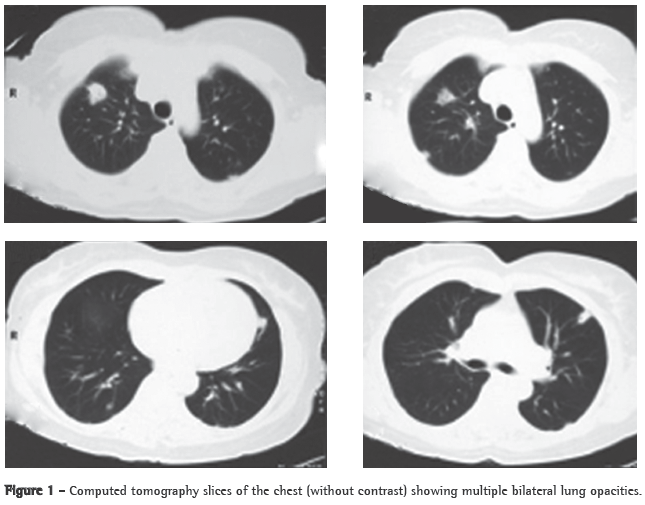

Abstract Lemierre's syndrome is characterized by acute oropharyngeal infection, complicated by internal jugular venous thrombosis secondary to septic thrombophlebitis, and by metastatic infections in various distant organs-most commonly in the lungs. We report a case of Lemierre's syndrome in a 56-year-old female who presented with right-sided neck mass and fever. Right internal jugular venous thrombosis was demonstrated on an ultrasound. A computed tomography scan of the chest revealed multiple opacities throughout both lungs. An open surgical biopsy was performed due to suspicion of pulmonary metastases. Anatomopathological examination revealed septic emboli in lung parenchyma. Retrospectively, the patient reported a history of pharyngitis two weeks prior to hospitalization. After the diagnosis had been made, the patient was treated with broad-spectrum antibiotics (cefuroxime for 7 days and azithromycin for 5 days; subsequently, because fever persisted, cefepime for 7 days). One month later, a computed tomography scan of the chest revealed resolution of the opacities.

A 56-year-old Caucasian female sought treatment in the emergency room presenting a painful, right-sided neck tumor for 5 days. The patient reported a dry cough and high fever for 3 days. She described herself as a nonsmoker. She was hypertensive and diabetic. She had experienced a myocardial infarction 3 years prior. At admission, the patient was dehydrated and afebrile (axillary temperature, 36.7°C). She presented normal respiration. Laboratory tests revealed increased erythrocyte sedimentation rate (92 mm). Ultrasound of the neck showed IJV thrombosis, and anticoagulation was started on post-admission day 4. A chest X-ray demonstrated at least two nodules in the left lung, one apparently cavitated and one with a diameter of 18 mm at its base, as well as an irregular lesion, 25 mm in diameter, in the right upper lung lobe. A transesophageal echocardiogram, performed in order to rule out endocarditis, demonstrated no vegetation. Due to the hypothesis of pneumonia, empirical treatment with oral cefuroxime (500 mg every 12 h) was started. A computed tomography scan of the chest revealed multiple bilateral lung opacities, with an aspect suggestive of metastatic implants (Figure 1). The patient was then submitted to fiberoptic bronchoscopy, the findings of which were normal. In the microbiological analysis of the bronchoalveolar lavage fluid, testing for acid-fast bacilli and fungi were negative, as were the cytopathologic study and cultures. Since the working diagnosis was metastatic neoplasm, the patient underwent surgical lung biopsy. The anatomopathological examination of the sample showed chronic suppurative inflammation with organizing abscesses in lung parenchyma. In view of the hypothesis of Lemierre's syndrome caused by jugular thrombosis accompanied by septic pulmonary embolism, the patient was questioned regarding the occurrence of tonsillitis at the onset of the disease. The patient had no recollection, but her daughter remembered that the patient had used oral amoxicillin (500 mg every 8 h for 10 days) for the treatment of tonsillitis some days prior to hospitalization. At hospital admission, the patient received a course of intravenous cefuroxime (750 mg every 8 h for 7 days) concomitantly with oral azithromycin (500 mg once a day for 5 days). Subsequently, because fever persisted, she was treated with cefepime (1,000 mg every 12 h for 7 days). A control computed tomography scan of the chest performed after this course of antibiotics showed nearly complete resolution of the opacities (Figure 2). The patient had been afebrile since the third day of the new course of antibiotics. No microorganisms were isolated from blood cultures or bronchoalveolar lavage cultures. Since there is no evidence that it is beneficial in cases of Lemierre's syndrome, anticoagulation was discontinued after 20 days.

Pulmonary involvement in this syndrome is extremely common (seen in up to 97% of the cases). Pulmonary lesions can manifest on the first day of sepsis. There can be intense pleuritic pain with dyspnea, and hemoptysis often occurs. Pulmonary auscultation can reveal localized crackling rales and pleural friction rub. Chest X-rays typically show multiple bilateral opacities and small pleural effusions. It is possible to detect cavitation on the first X-ray. There can be rapid progression of the lesions, even with the use of antibiotics. Empyema develops in 10% to 15% of cases. Abscess, pneumothorax and pneumatoceles have been described. After contrast administration, there is peripheral enhancement of the lesions with central areas of decreased attenuation. The differential diagnosis should be made with pneumonia (acute bacterial, atypical, aspiration and staphylococcal pneumonia).(1,2,11-14)